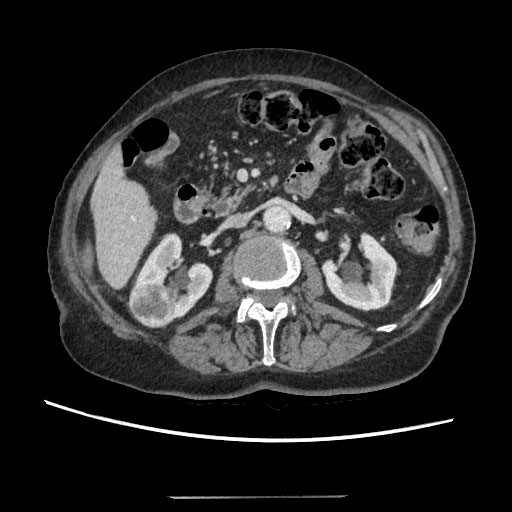

75-years-old woman presented with right kidney tumor using ultrasound. Two tumors were detected on CT (Figure 1). The conclusion of a CT scan: In the right kidney mid/lower pole 16 mm in diameter hypervascular tumor, more endophytic, about 7 mm till the collecting system of the kidney (Nephrometry scale 5a). The second tumor in the right kidney is approximately 37 × 28 × 44 in size, located in the upper/mid thirds of the kidney, more laterally, polycyclic, nonhomogeneous with necrosis, unevenly accumulates contrast agent, more endophytic, in contact with collecting system of the kidney. A biopsy was performed. Moderately-differentiated (G2) papillary adenocarcinoma, I type was found. Under intravenous anesthesia, percutaneous ultrasound-guided microwave thermal ablation was carried out. Under ultrasound guidance two short tip needles were inserted into the tumors and microwave thermal ablation was performed for 15 minutes using 35 W. The tumors changed in visually as were seen on ultrasound. The needles were removed after procedure. No perioperative or post-operative complications were observed. After 2 weeks a large amount of urine began to leak through the puncture site on the right flank. Approximately 1.5 l of urine on a daily basis. CT was performed: Fistula from the mid calyx was found (Figure 2). Collection of fluid around the fistula, by the abdominal wall. It was decided to put a stent in the right ureter. Nephrostomy was technically impossible due to the absence of hydronephrosis. Because of ureteral stenosis, ureteroscopy was unsuccessful. Right ureteral stenting was performed under the X-ray control. Position of the stent was appropriate. The patient was released home. There was no urine coming through the fistula, but after two weeks, the leaking of urine reoccurred. After two months patient was admitted to the hospital for ureteroscopy and the replacement of the stent. The urologist was unable to perform ureteroscopy because the proximal end of the stent was in the infiltrated tissue, probably outside the ureter. It was impossible to replace the stent, the stent was removed. Due to excessive discharge of the urine through the fistula and erythema it was decided to perform right kidney resection, but it was technically unavailable because of fibrosis and suppuration of the surrounding tissues. Nephrectomy was performed. Post-operative time without any complications. Histological examination showed no residual papillary adenocarcinoma in the kidney.

Figure 1: Two tumors were detected on CT. View Figure 1